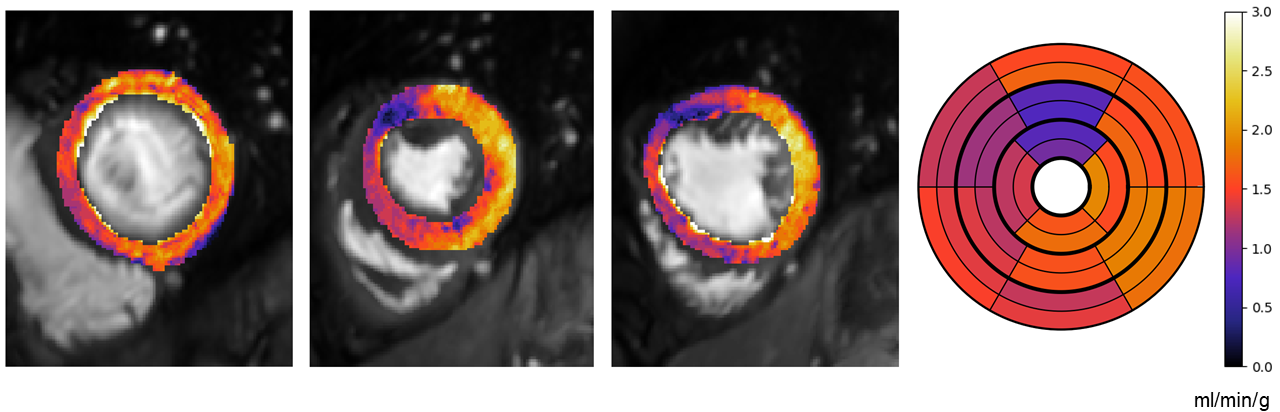

\printthesisindex